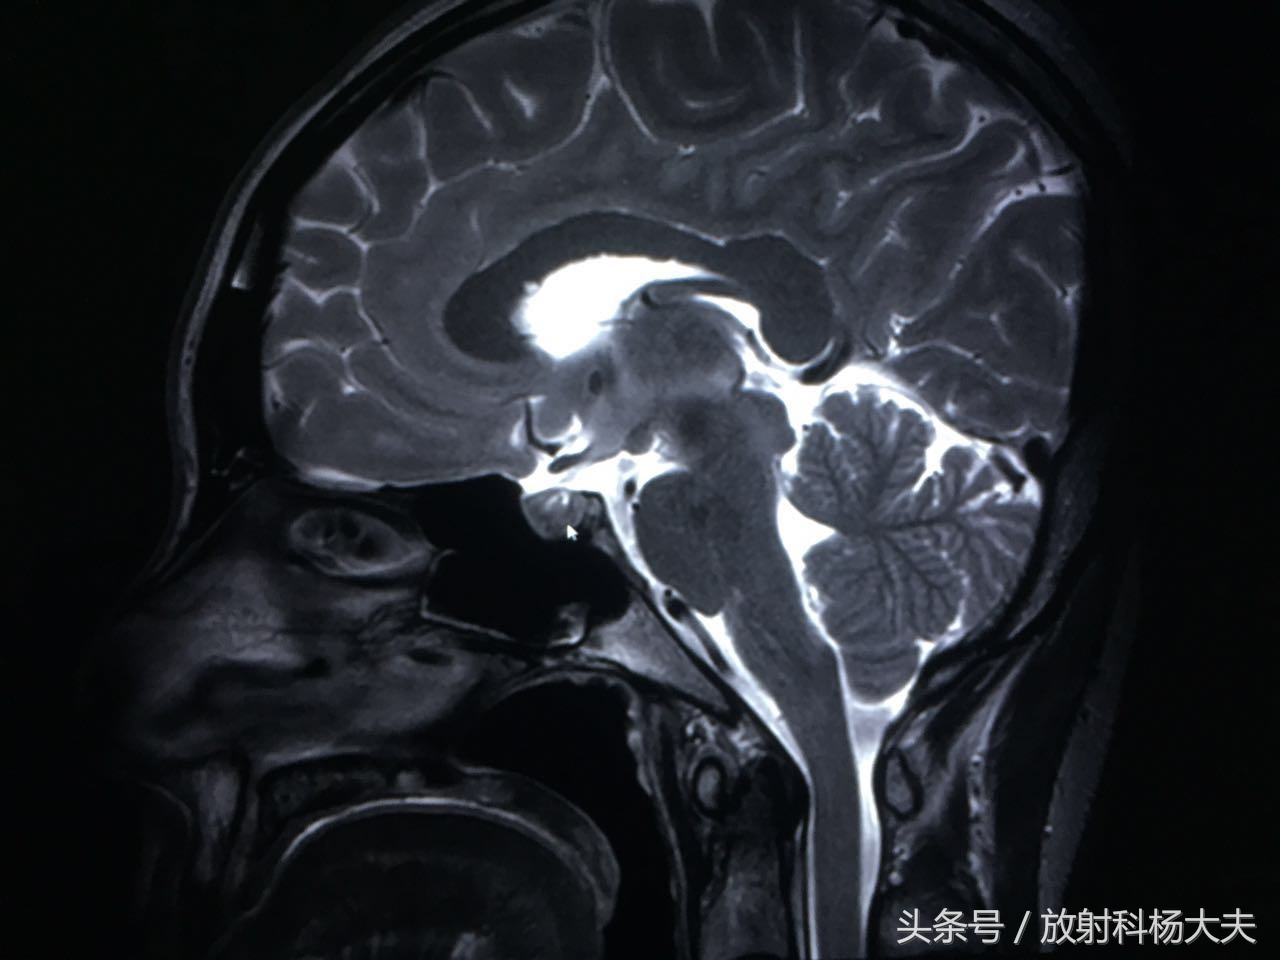

图像出来了,我们可看到垂体内的异常信号(短箭头所指地方),呈长T1混杂T2信号。

T2WI白箭所示为垂体,这个器官很小,但很重要

动态增强扫描可见延迟强化,其延迟期扫描强化程度仍低于周围正常腺体。余垂体强化均匀。

箭头所示的为垂体的瘤子